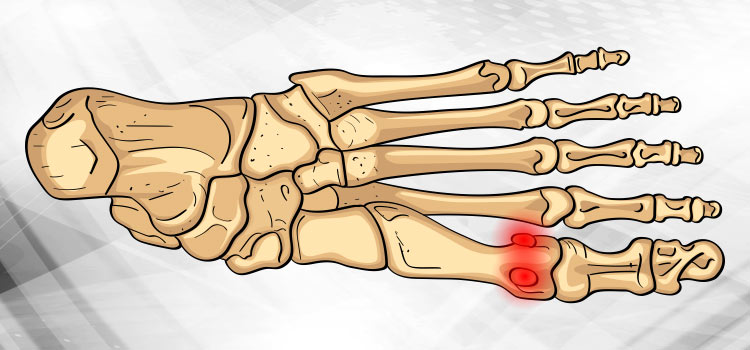

Sesamoidite

A sesamoidite é uma inflamação que atinge dois ossos dos pés. Esses, por sua vez, localizados entre a planta do pé e o halux (“dedão”). Se não tratado de prontidão, a patologia poderá se agravar e até evoluir para uma necrose (morte do tecido dos ossinhos). Por isso um médico ortopedista especialista em pés deve ser consultado o quanto antes.